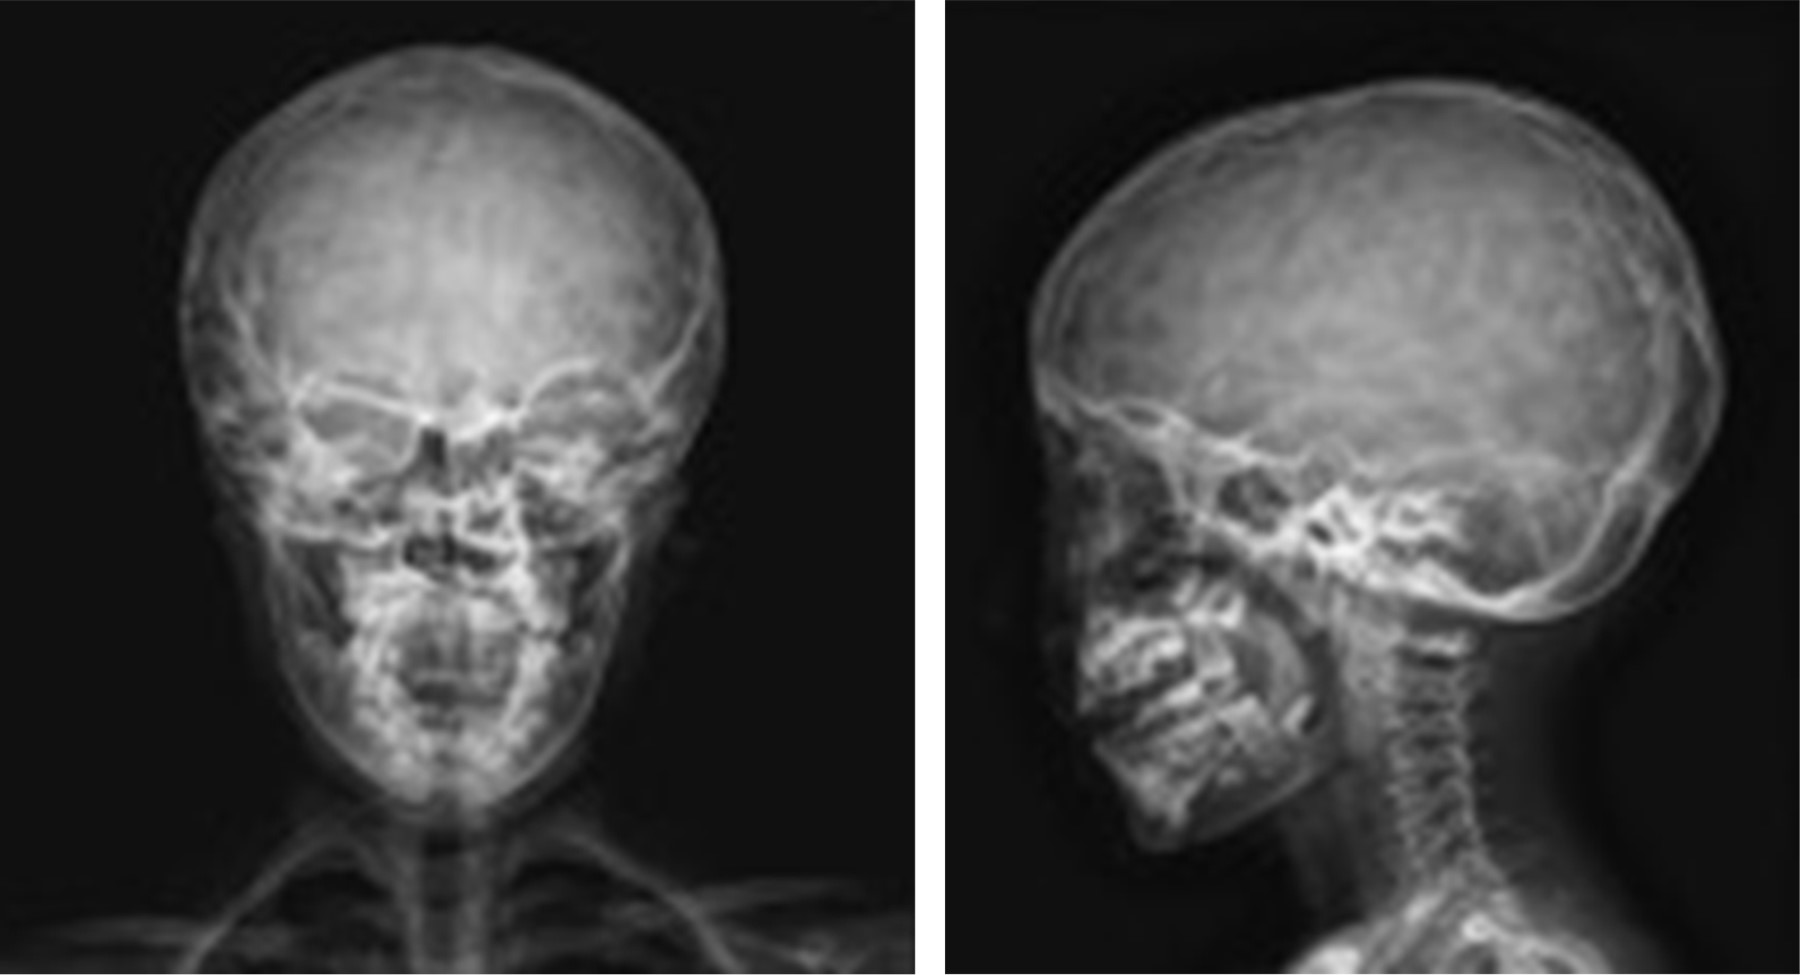

Ante la presencia de los hallazgos radiográficos, se deben considerar el diagnóstico diferencial con craneolacunia9 también llamada "cráneo fenestrado", "luckenschadel" –en alemán– (Figura 4),10 o bien, cráneo "en burbujas de jabón" (Figura 5).10 Esta entidad se desarrolla en la vida fetal, y se puede observar radiológicamente desde el nacimiento, desapareciendo entre el quinto y sexto mes de vida.11

La craneolacunia es una cráneo-displasia12 del hueso membranoso en donde la tabla interna de los huesos de la bóveda tiene un patrón de osificación heterogéneo, irregular y discontinuo dado por crestas de hueso normal, que delimitan defectos óseos redondeados (lagunas) en los cuales hay disminución en el espesor de la tabla ósea interna, en algunas zonas el defecto es tan grave que sólo hay periostio y duramadre cubriendo al encéfalo, de ahí el término "lacunar skull".12,13 Se presenta desde el nacimiento (a diferencia del cráneo martillado que suele detectarse durante la infancia) y generalmente coexiste con defectos del tubo neural (meningocele, mielomeningocele, encefalocele, espina bífida, paladar hendido y malformación Arnold Chiari de tipo II). Algunos autores refieren que se afecta con mayor frecuencia los huesos parietal y occipital.13 En la Tabla 1, se describen datos para diferenciar la craneolacunia del cráneo en cobre batido.

Figura 4